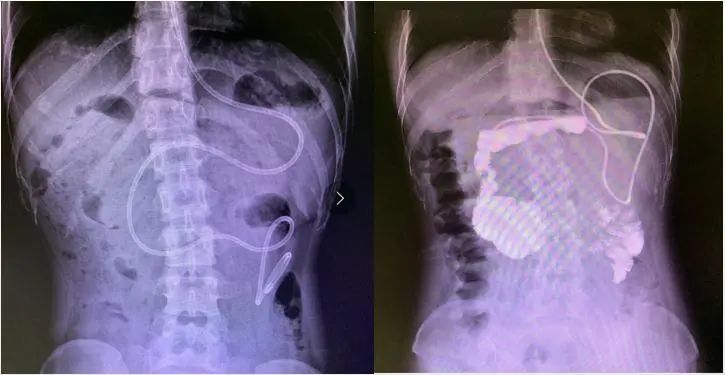

患者入院前肠腔大便蓄积及肠管显著扩张

术前肠道微生态预处理

经历一疗程肠道微生态治疗后,小李可耐受全量肠内营养,营养状况显著改善,但由于长期便秘,肠管仍有较大程度扩张。考虑到患者长期生活质量,同时患者经过一疗程肠道微生态治疗后,身体体质明显改善,手术耐受性可,考虑患者年轻且尚未生育,李宁教授为患者制定根治性手术方案,于2020-4-28在全麻下行腹腔镜下全结肠切除术+回肠直肠吻合术,作为中国医促会加速康复外科分会主任委员单位,科室加速康复外科护理小组按ERAS理念制定了康复方案,患者术后第二天开始排气排便,第三天开始排便,患者因长期便秘导致胃肠排空障碍,我们通过鼻饲管给予短肽型肠内营养支持治疗,并逐渐恢复口服进食,患者于术后1周顺利出院。